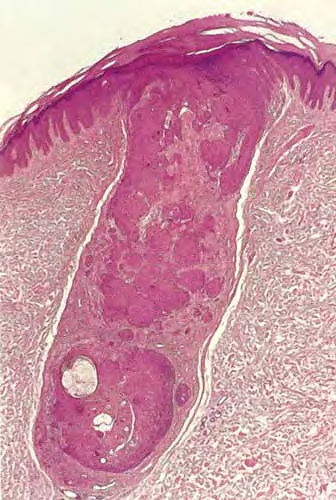

Inverted follicular keratosis = التقران الجرابي المقلوب